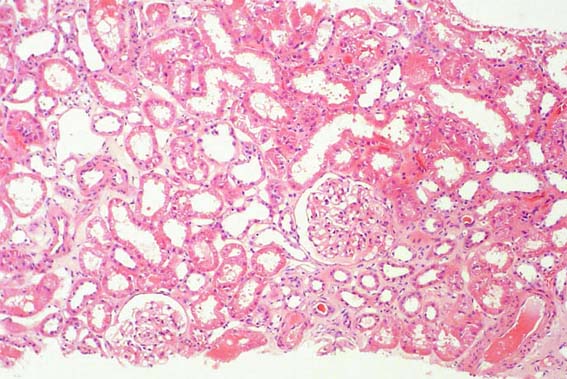

Figura 1.

H&E, X100.